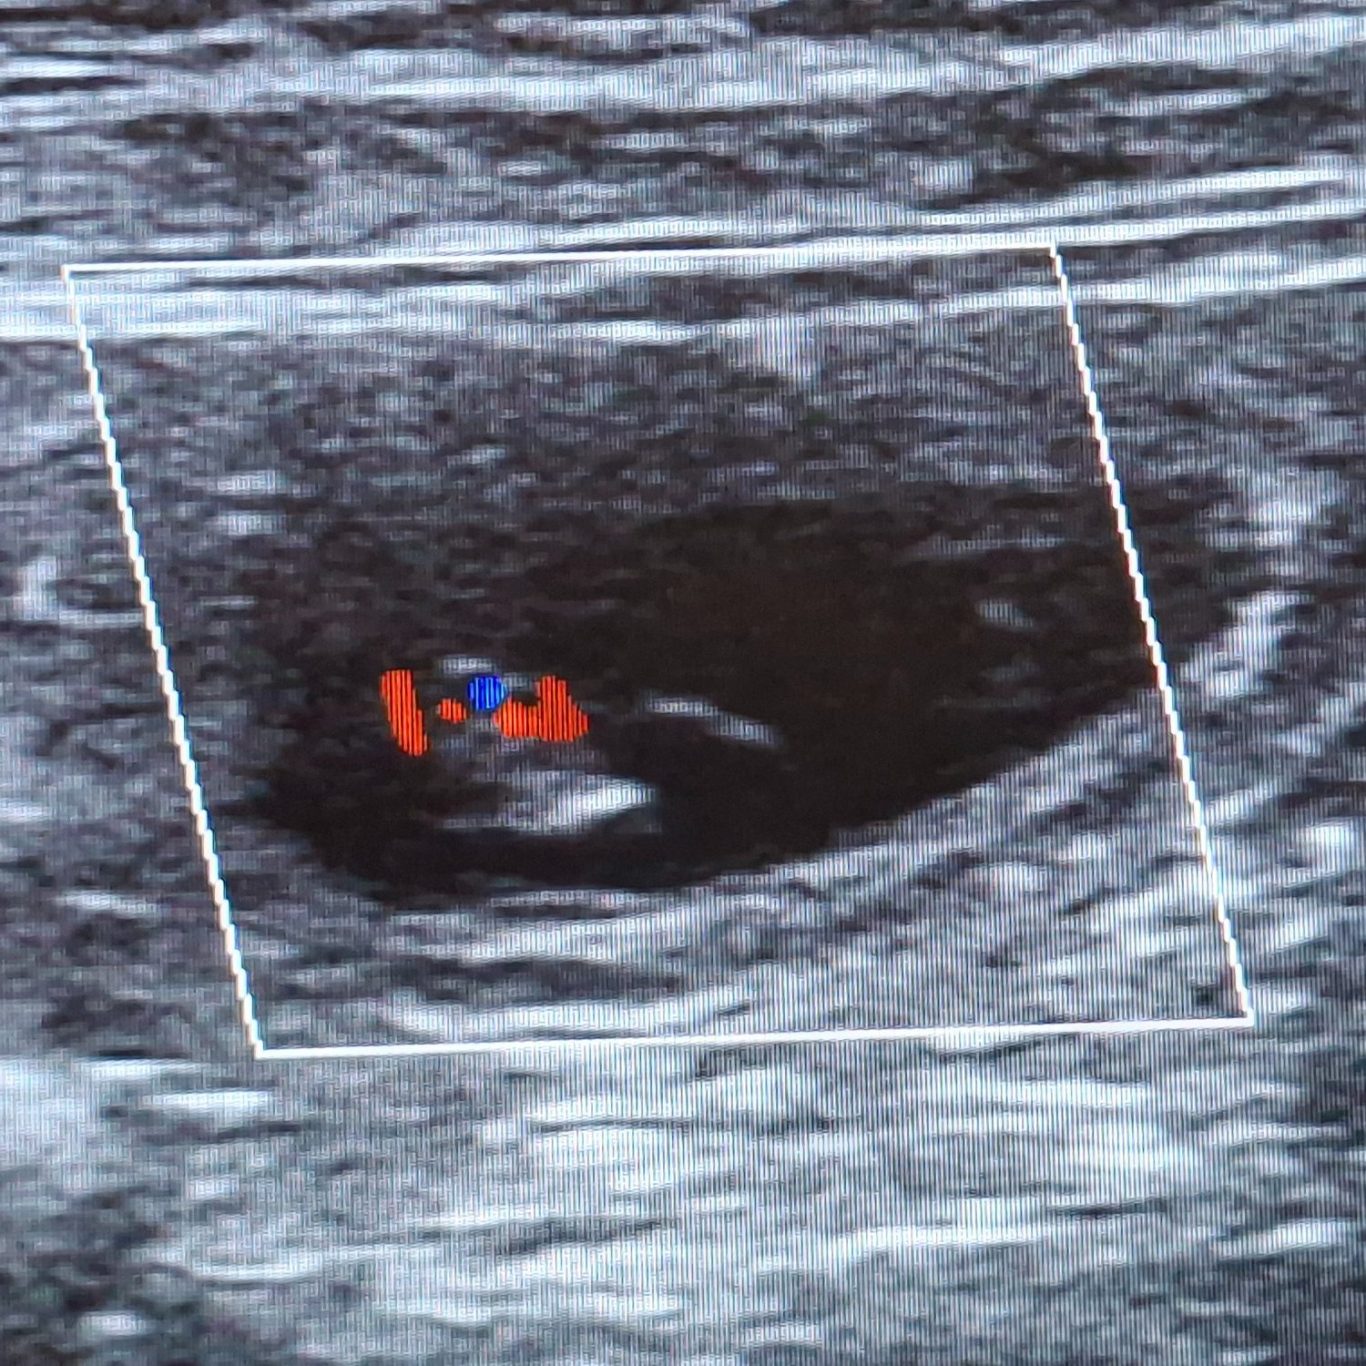

Endlich hatten wir den ersten Ultraschall und wir haben tolle Neuigkeiten

!!Kuba ist trächtig!!

Die letzten Tage waren für mich sehr sehr hart. Die Spannung war kaum auszuhalten. Ich wollte es jetzt endlich bestätigt haben, dass unsere Kuba trächtig ist. Ihr Verhalten und ihr Körper haben sich aber schon sehr verdächtig verändert. Sodass es heute eigentlich klar war, dass wir mit dem Ultraschall fündig werden. Wir haben nur einen kleinen Bereich geschallt und auch nicht lange, damit es für sie nicht zu anstrengend wird. Uns war nur wichtig zu sehen, dass es geklappt hat und die Kleinen leben. Alle Herzchen die wir gefunden haben schlugen ganz stark und alles sieht sehr gut aus.